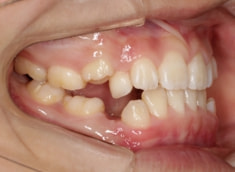

治療前